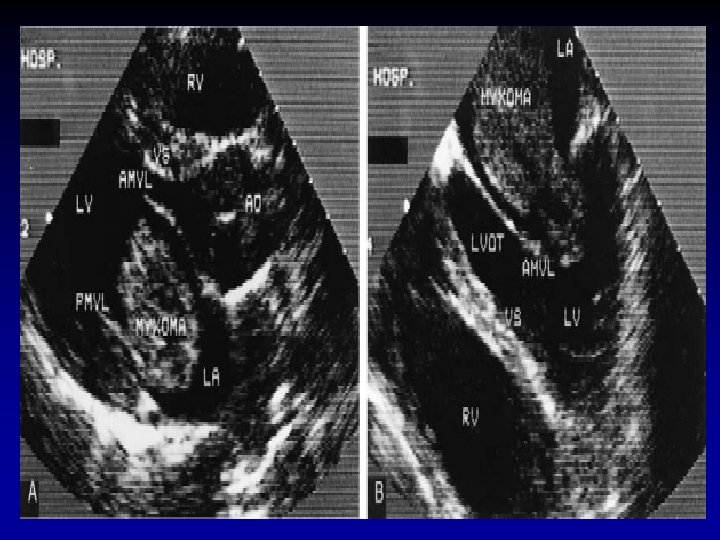

LABORATORIO DIAGNÓSTICO Ecocardiografía • Test de tamizaje • Tamaño del tumor, movilidad, vecindad • Consecuencias hemodinámicas • Medio de contraste • TE • Mejor resolución • TT subóptima

TUMORES BENIGNOS MIXOMA AURICULAR • Rx • 50% tienen AI grande y signos de HTP • 30% Rx normales • Ecocardiografía • Diagnóstico • Identificar sitio de unión del tumor • Descartar compromiso valvular • Descartar masas múltiples • Planear cirugía • Control Pos. Qx

TUMORES BENIGNOS MIXOMA AURICULAR • Neoplasia primaria cardiaca mas común en adultos • 75% en AI • 90% están entre 30 y 60 años • Principalmente en mujeres (66%) • Origen en fosa ovalis • Sospechar malignidad si esta en pared posterior • Tamaño promedio 5 -6 cm

TUMORES BENIGNOS MIXOMA AURICULAR • Patología • Pedículo unido a septum interatrial • Suave, gelatinosa y friable • 10% son calcificadas • Requiere identificación de cell mixomatosa • Focos de hematopoyesis extramedular